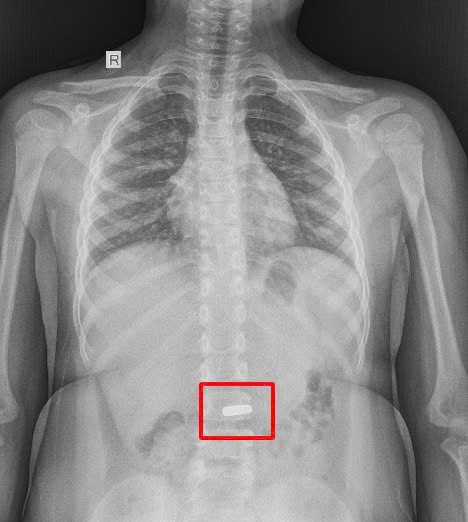

Dị vật nam châm hình trái tim trong dạ dày

Tại bệnh viện, bé được thăm khám và chụp X-quang. Hình ảnh ghi nhận trong dạ dày có dị vật là nam châm với cạnh dài khoảng 20mm.

Phim chụp dạ dày có dị vật là nam châm với cạnh dài khoảng 20mm - Ảnh BVCC